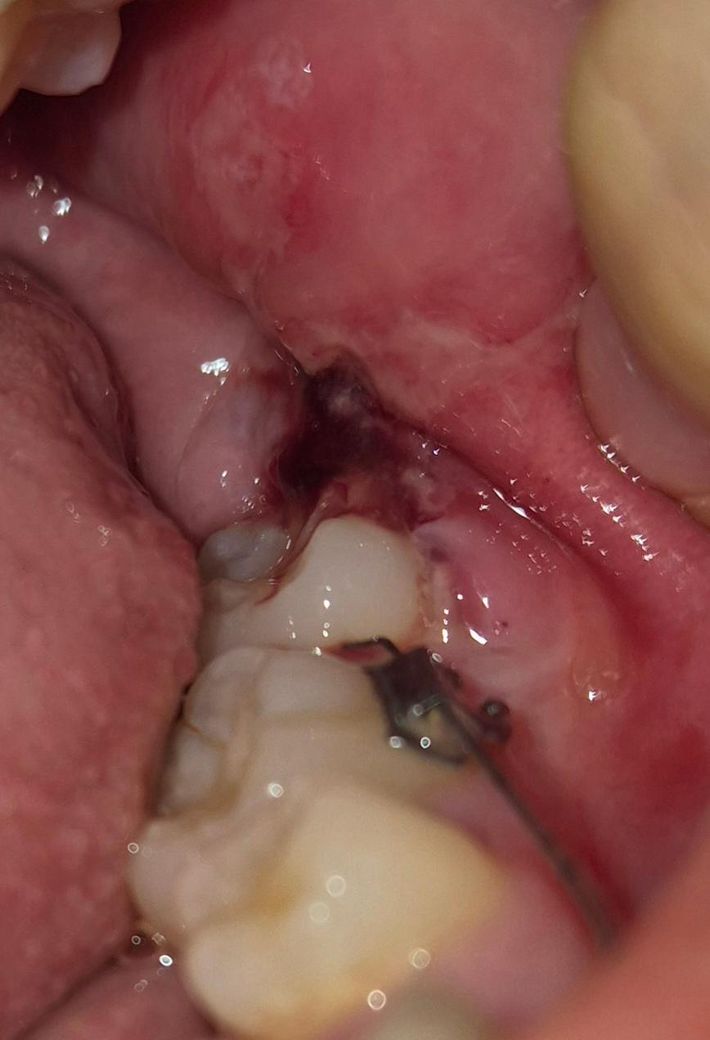

어제 거즈 4번정도 갈면서 지혈했고 1번째 사진은 오전10시쯤밥, 약먹고 난뒤입니다. 거즈문 상태로 자고 4시쯤 일어나서 밥먹고 약먹었는데 피맛이 아니라 이상한 맛 나는데 감염된 걸까요? 2,3번째사진

• 2번 째 사진